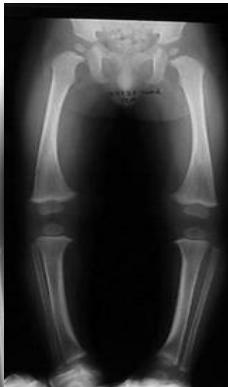

Radiological Assessment

Indications: X-ray when severe or possibly pathologic

Recommended Views:

- Standing AP film: Long film (hips to ankles) with patellae directed forwards

Radiological Parameters to Assess:

- Medial Physeal Slope

- Femoral-Tibial Axis

Conditions to Look For:

Rickets

Tibia vara (Blount’s disease)

Epiphyseal injury

Angle measurements

Medial Physeal Slope

Femoral-Tibial Axis